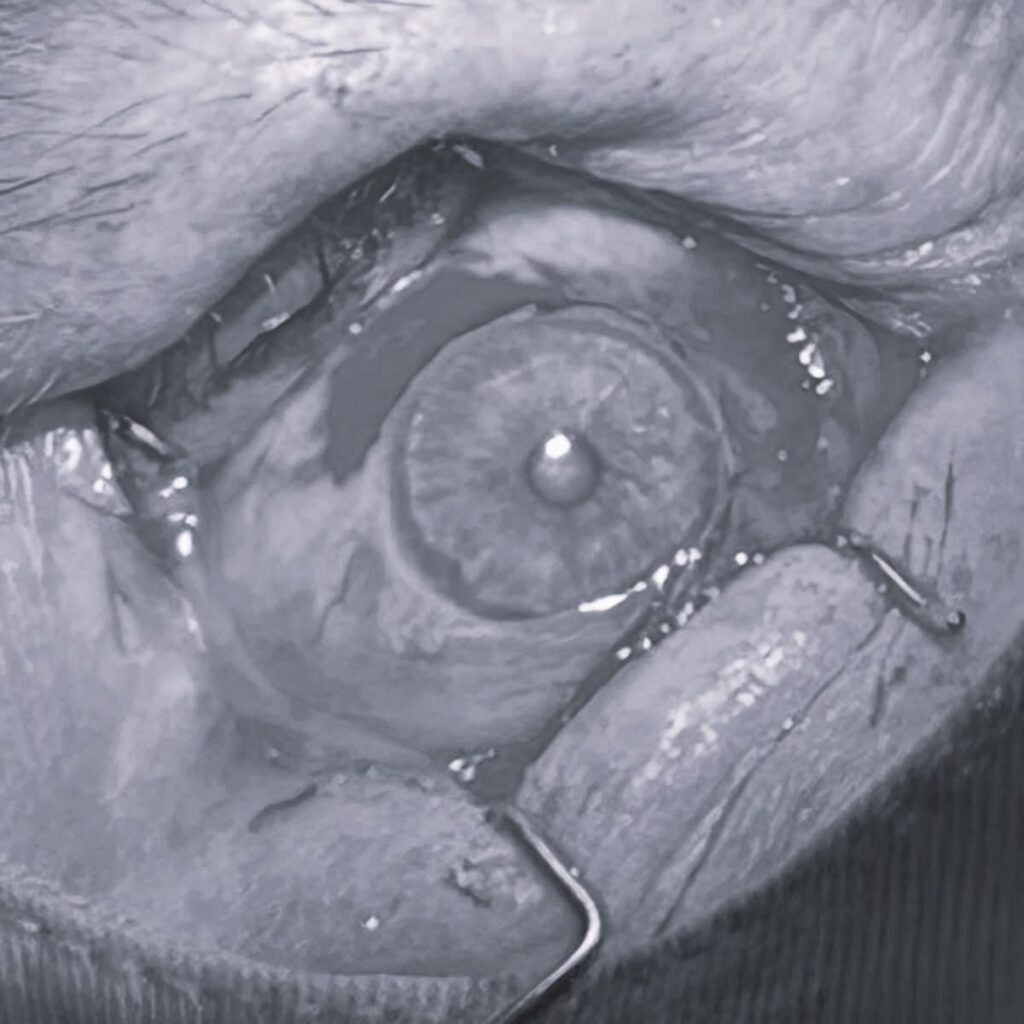

Este vorba despre chirurgia pterigionului cu autogrefa conjunctivala, o tehnica moderna, utilizata in special in cazurile avansate sau recidivante, care ofera pacientilor sanse mai mari de vindecare si de mentinere a acuitatii vizuale.

Tratamentul chirurgical presupune extirparea completa a pterigionului, urmata de prelevarea unei portiuni de conjunctiva sanatoasa dintr-o alta zona a ochiului. Aceasta este ulterior transplantată la nivelul zonei afectate, cu scopul de a reduce riscul de recidiva. Tehnica autogrefei conjunctivale este considerata, la nivel international, standardul de aur in tratamentul chirurgical al pterigionului.